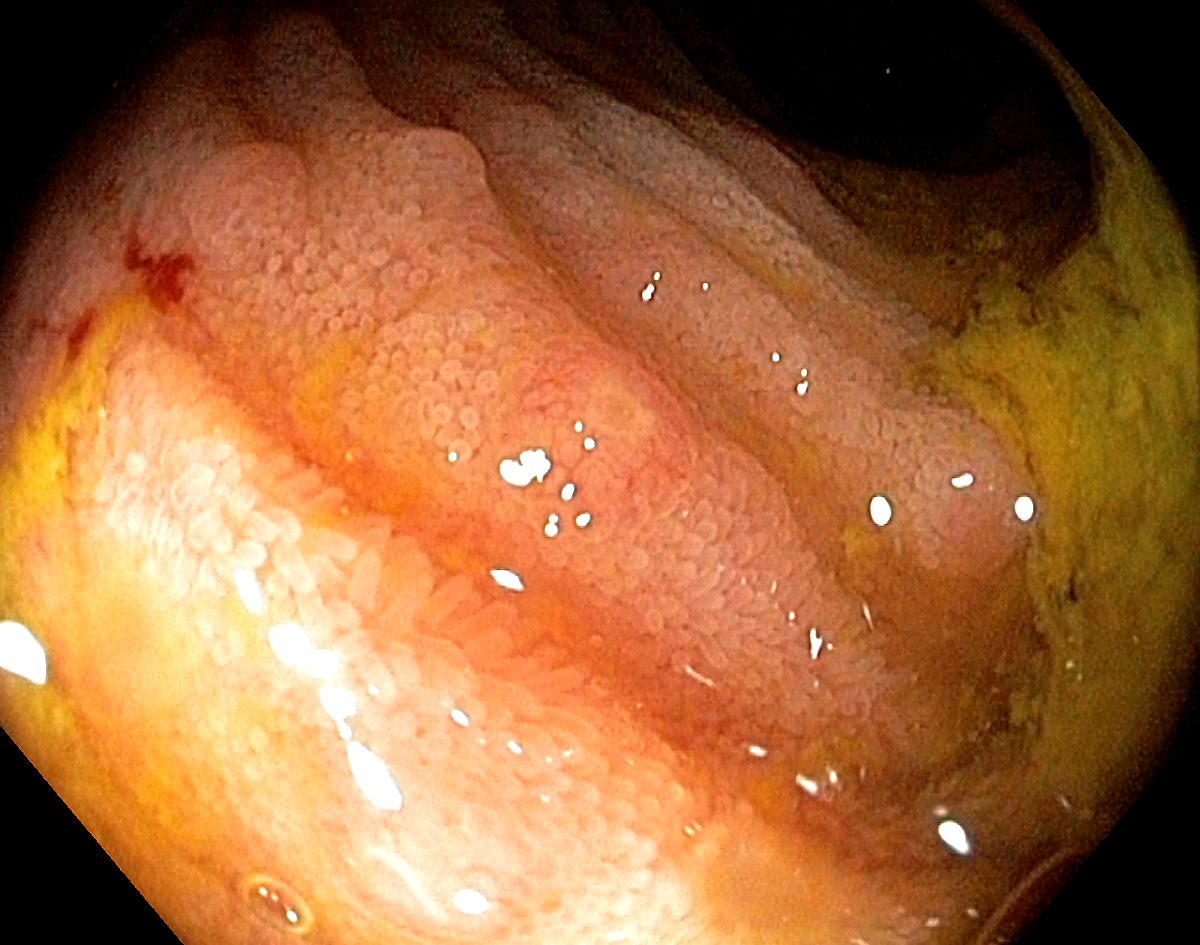

Normal villi in the terminal ileum

The terminal ileum with clearly visible mucosal villi and some lymphoid hyperplasia

Villi in the terminal ileum. The bowel content is quite dark due to bile.